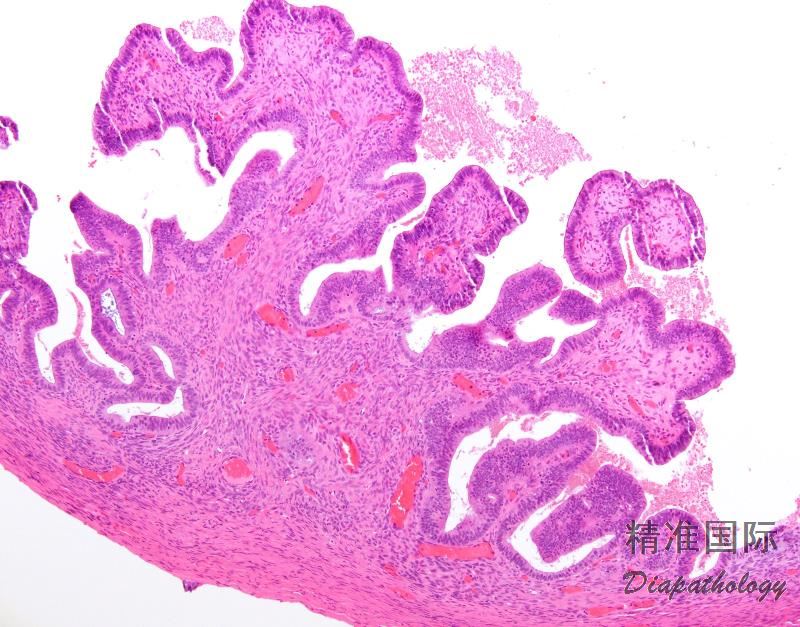

卵巢子宫内膜样囊腺瘤/腺纤维瘤

Ovarian endometrioid cystadenoma/adenofibroma

囊性肿物,被覆良性子宫内膜样腺上皮,无子宫内膜样间质。当出现致密纤维瘤样成分时称为子宫内膜样腺纤维瘤。

上皮成分呈分支管状腺体和囊肿,常类似于增生期子宫内膜或轻度增生的子宫内膜腺上皮,细胞呈高柱状,细胞核卵圆形,染色质粗,有小核仁;细胞质嗜碱性至嗜双色性;

上皮常有纤毛,类似输卵管上皮;

间质常为致密的纤维,局灶区域类似卵巢皮质,腺纤维瘤时间质呈纤维瘤样增生;